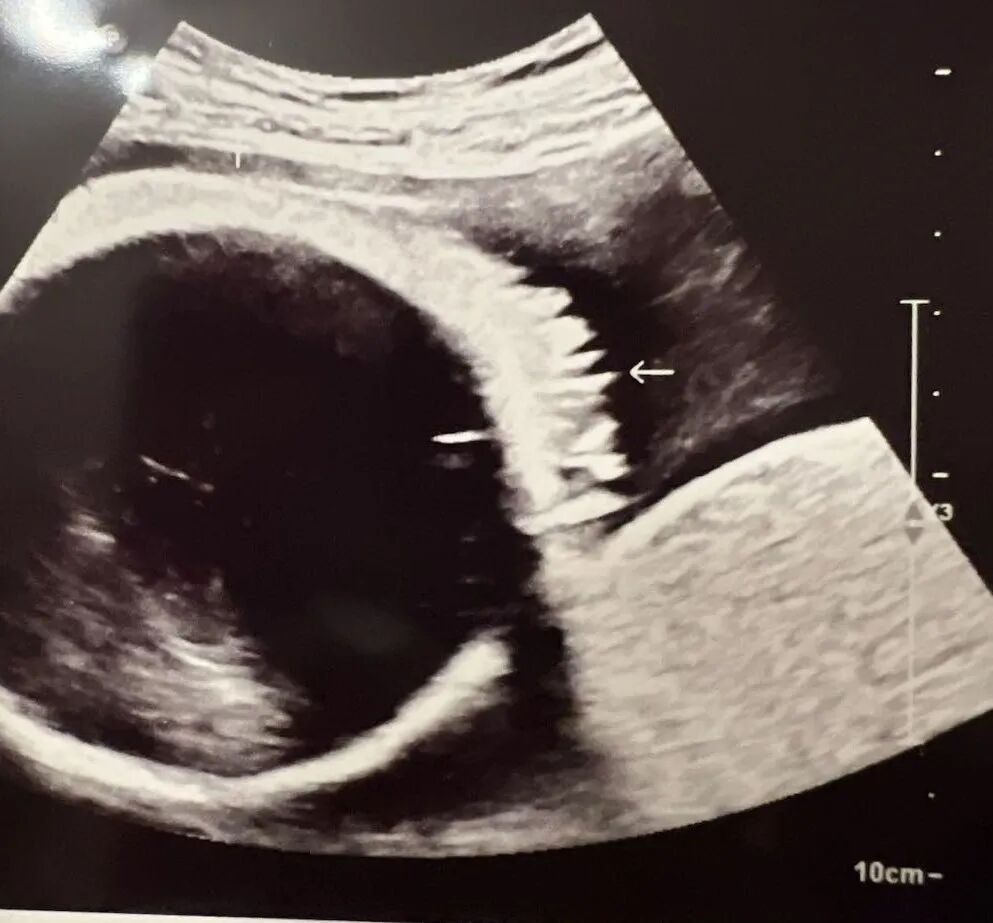

我们单身准妈妈终于迎来了宝宝的喜讯!在我们的帮助下,她找到了心仪的捐赠者,制作出了优质的胚胎。爱妈N特意飞来圣地亚哥的诊所进行移植,一切都进行得非常顺利。今天来诊所进行B超检查,验孕结果成功,虽然宝宝刚刚开始萌芽,但心跳却非常有力,达到了117bpm。我们已经满怀地期待着一个高颜值的混血宝宝的到来了!